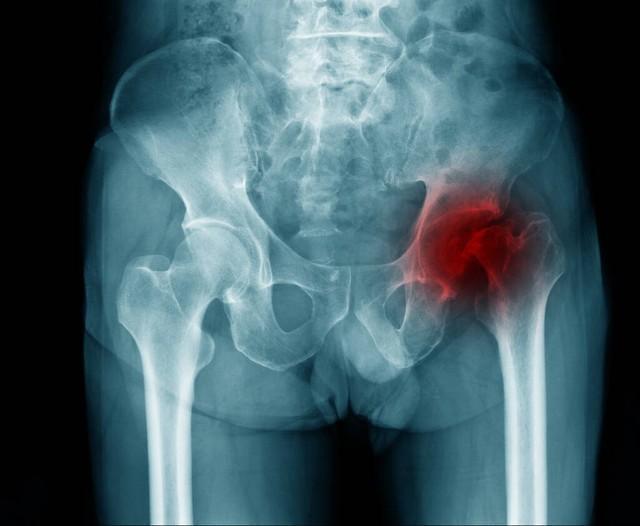

骨頭壞死是指骨組織因各種原因?qū)е卵汗?yīng)不足,從而使骨細(xì)胞死亡和骨組織破壞的過(guò)程,骨頭壞死的原因包括創(chuàng)傷、感染、長(zhǎng)期應(yīng)用激素、骨質(zhì)疏松等,骨頭壞死后,患者可能出現(xiàn)疼痛、腫脹、活動(dòng)受限等癥狀。

骨頭壞死后能否恢復(fù)取決于病情的嚴(yán)重程度、發(fā)現(xiàn)時(shí)機(jī)及治療方法,在骨頭壞死的早期階段,通過(guò)適當(dāng)?shù)闹委熀涂祻?fù)措施,有可能實(shí)現(xiàn)骨組織的再生和恢復(fù),如果病情嚴(yán)重或治療不及時(shí),可能會(huì)導(dǎo)致骨組織的不可逆損害,影響恢復(fù)。

2、手術(shù)治療:對(duì)于嚴(yán)重骨頭壞死,可能需要進(jìn)行手術(shù)治療,如骨移植、關(guān)節(jié)置換等,手術(shù)治療的效果因個(gè)體情況而異,需在專業(yè)醫(yī)生的指導(dǎo)下進(jìn)行。